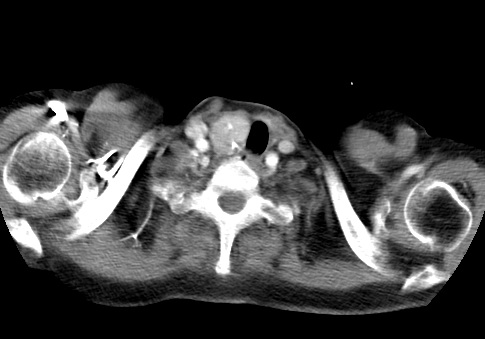

标题: CT23982:女67岁,胸部扫描时发现,甲状腺瘤? [打印本页]

标题: CT23982:女67岁,胸部扫描时发现,甲状腺瘤?

右侧甲状腺腺瘤!支持!不排除甲状腺癌可能!建议手术切除!

右侧甲状腺占位性病变,性质待定(甲状腺腺瘤?);建议:必要时行进一步检查。

右侧甲状腺占位性病变,性质待定(甲状腺腺瘤?);

右侧甲状腺占位性病变,性质待定(甲状腺腺瘤?);建议穿刺活检。

右侧甲状腺占位性病变,甲状腺腺瘤可能,建议穿刺活检。